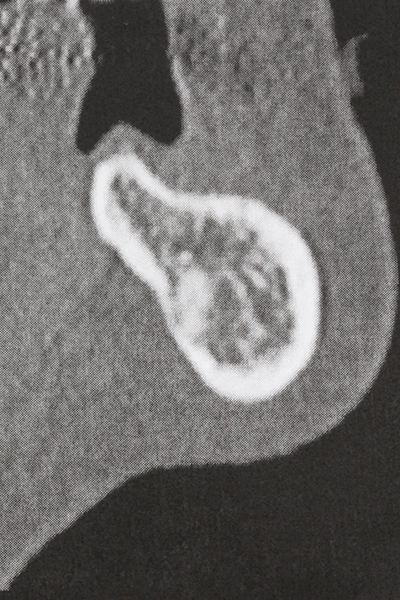

There are additional applications in sinus surgery. Pathologies and foreign bodies can be removed from the sinus after concentric preparation of a generally trapezoid bone cover in the facial sinus wall. The bone cover is repositioned on conclusion of the intra-antral operation component and secured by wedging or adaptive sutures to prevent dislocation.